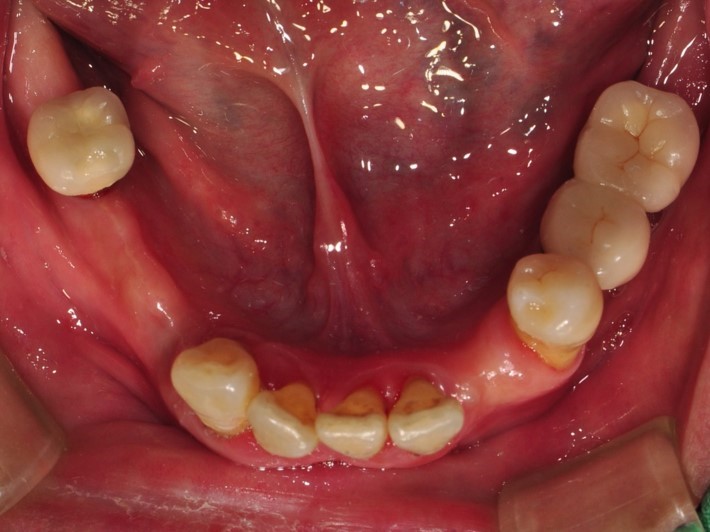

治療前-上顎

治療前